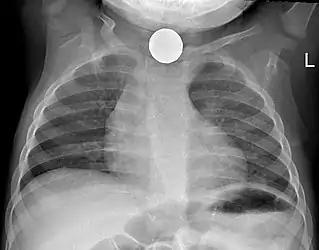

Tension pneumothorax

Tension pneumothorax is an emergent condition in which air gets trapped in the space between the chest wall and the lung. This space is referred to as the pleural space. Because air can't escape from this space, the pocket of air grows larger and larger which results in collapse of the lung closest to the pneumothorax. Forces are transmitted to the mediastinum and effectively "push" the mediastinal structures to the opposite side of the chest. [5]